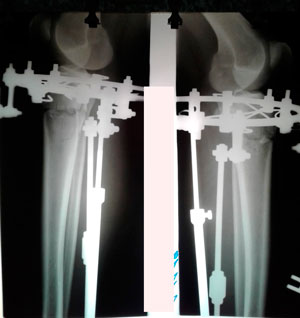

перед крутками

IMG_6432-15-10-19-09-33.JPG

на фиксации

Вложения

IMG_6909-05-11-19-07-59.JPG

IMG_6908-05-11-19-07-59.JPG

IMG_6907-05-11-19-07-59.JPG